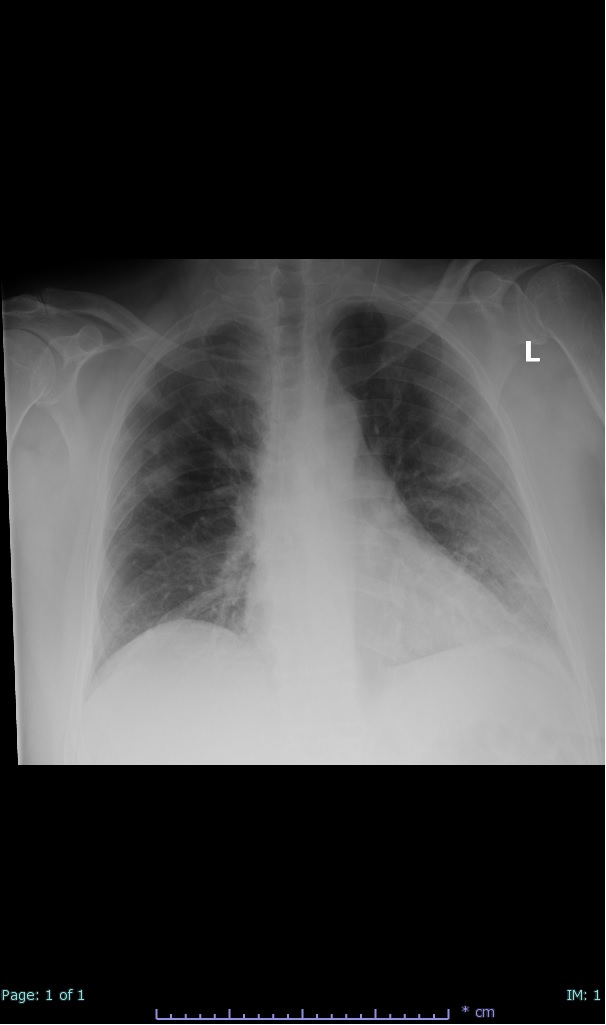

- 66% had some + CXR finding I could correlate to a CT finding